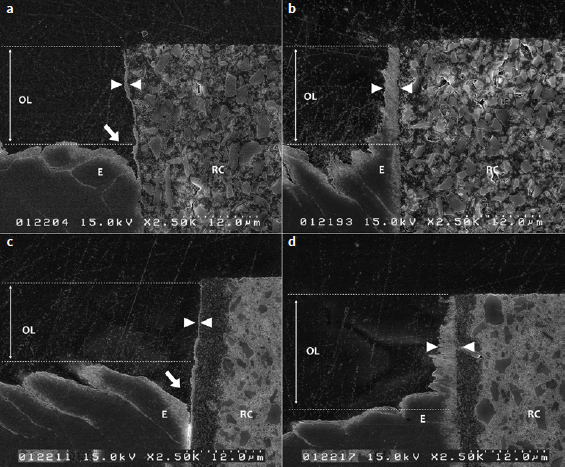

Materials and methods: Two DCRC were used in 4 groups: Panavia V5 in self-etch (V5NE) and etch-and-rinse mode (V5E); and Estecem II in self-etch (ENE) and etch-and-rinse mode (EE). For ABRZ observation, the bonded interface was subjected to a demineralizing solution. The morphological attributes of the interface and etching patterns were observed using FE-SEM. For μ-SBS, cylinders with a 0.79-mm internal diameter and 0.5-mm height were made with DCRC and tested in shear after 0, 5000, and 10,000 thermal cycles (TC) (5°C and 55°C) (n = 10).

Results: The formation of an enamel ABRZ was observed in all groups with different morphological features between self-etch and etch-and-rinse groups. A funnel-shaped erosion beneath the interface was present using V5NE and ENE modes where enamel was dissolved, while ABRZ formation was confirmed and no funnel-shaped erosion was noticed using V5E and EE. No significant differences in μSBS were observed between resin cements. However, significantly lower µSBSs were recorded when the self-etching mode was used. Thermocycling resulted in a significant reduction in µSBS for all groups.